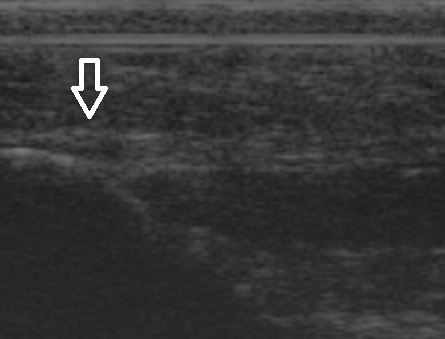

De podoloog Arnhem maakt een echo van uw voet om te kunnen zien of er sprake is van fasciitis plantaris of een hielspoor. Combinaties van beide klachten komen vaak voor.

Mortonse Neuralgie is door de podoloog goed te diagnosticeren. De neuroom ( zenuwverdikking) is soms duidelijk zichtbaar tijdens ons echo-onderzoek. Compressie van alle middenvoetsbeentjes, het knijpen in de voorvoet zal de klachten provoceren. Vaak horen we bij het knijpen in de voorvoet ook een klik (Mulder’s Kliktest). Deze klik wordt veroorzaakt door het verspringen van het neuroom tussen de middenvoetsbeentjes van de derde en vierde teen.